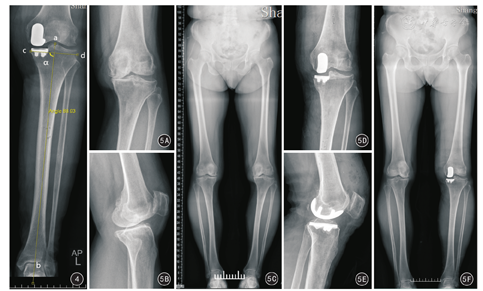

所有患者在术前常规进行标准双下肢正位全长X线检查,以此来测量患侧膝关节的内外翻畸形角度。术后5 d内拍摄双下肢正位全长X线片和患侧膝关节正侧位X线片,测量术后患侧膝关节畸形角度,并测量冠状面上假体内外向轴线与胫骨机械轴的夹角(图4),与术前计划的假体位置目标值(内翻1°)进行比较,评估冠状位上胫骨假体的植入位置以及手术方案实施的精确性。X线片影像学角度测量利用计算机软件(金仕达卫宁PACS系统,金仕达卫宁软件股份有限公司)由2位未参与手术的医生分别独立手动完成,以2位测量者所测数值的平均值作为最终测量结果。股骨头中心与膝关节中心的连线定义为股骨机械轴,膝关节中心与踝关节中心的连线定义为胫骨机械轴,股骨机械轴与胫骨机械轴的夹角定义为膝关节畸形角度。

截至2017年1月30日,20例患者随访时间为8~20周,平均14.1周。本组5例患者接受一期双侧UKA,故共有25膝接受膝关节功能评分及术前术后影像学测量分析。末次随访时:患侧膝关节的KSS临床评分由术前的(57±13)分提高至(90±6)分,功能评分由术前的(48±18)分提高至(79±12),差异均有统计学意义(t=14.94、10.014,P值均<0.01)。20例患者影像学结果评估满意(图5),膝关节内翻畸形角度由术前的8.7°±4.2°纠正至术后的4.0°±3.5°。25膝UKA中,胫骨假体内外向轴线与胫骨机械轴的夹角为内翻0~3.9°,平均内翻1.7°±1.2°,其中内翻0~1.0° 10膝,>1.0°~2.0° 6膝,>2.0°~3.0° 5膝,>3.0°~3.9° 4膝,胫骨假体位置处于内翻3°以内占84%(21/25),无一例出现假体外翻。相对于术前计划设定的1°内翻的目标值,术后胫骨假体冠状位角度偏差平均偏差角度为1.1°±0.9°,其中21膝(84%)<2°,4膝(16%)偏差2°~<3°。2家医院2组病例胫骨假体冠状位角度与目标位置的偏差分别为1.2°±1.1°(n=10)和1.0°±0.6°(n=15),差异无统计学意义(t=0.421,P>0.05)。